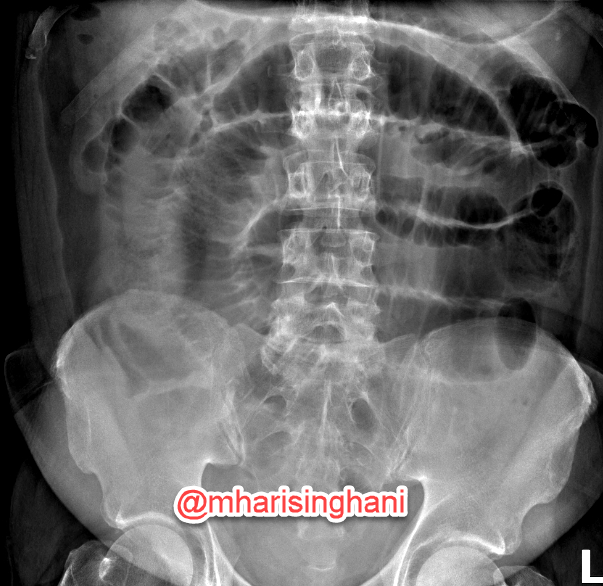

@mharisinghani Great example of an uncommon but very helpful sign to recognize fluid-filled small bowel in obstruction. And confirmation that upright or decubitus views are important.